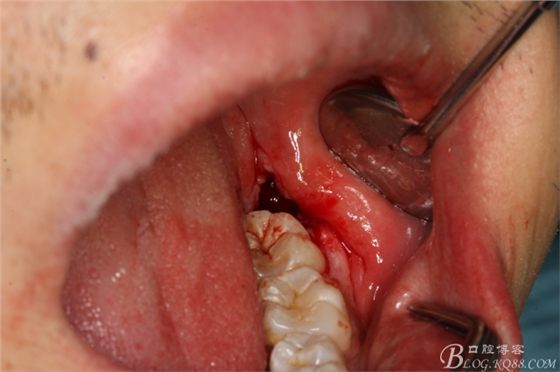

圖4.采用不切開(kāi)、不翻瓣、利用暴露出來(lái)的牙冠進(jìn)行潛掘式分牙

圖5.高速渦輪鉆舌側(cè)潛掘法橫斷牙冠